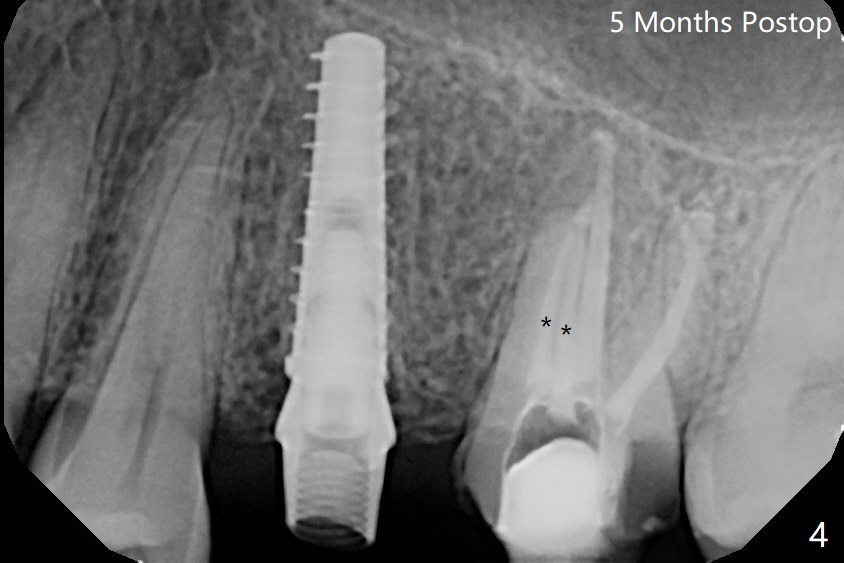

Due to misinterpretation of drill sequence, osteotomy is overprepared in depth (1.5 to 3 mm). When a 4x11 mm dummy implant is placed with > 50 Ncm (Fig.1,2), over placement is ignored. A 4x13 mm final implant is placed with fairly good torque, but it is deeper than expected. When it is backed up, primary stability is lost, in spite of placement of allograft in the osteotomy. Final torque is 15 Ncm. When a 4.5x4(2) mm abutment is placed, the underlying implant turns (Fig.3). A splinted provisional is fabricated at #13 and 14. RCT is retreated 5 months postop (Fig.4 *). An abutment with longer cuff is placed before impression (8.5 months postop, Fig.5). When the crowns of #13 and 14 are delivered, the former looks short and noncosmetic, although the gingiva will grow downward to close the gap (Fig.6). Ideally the gap should be closed with porcelain with overhang (Fig.7).